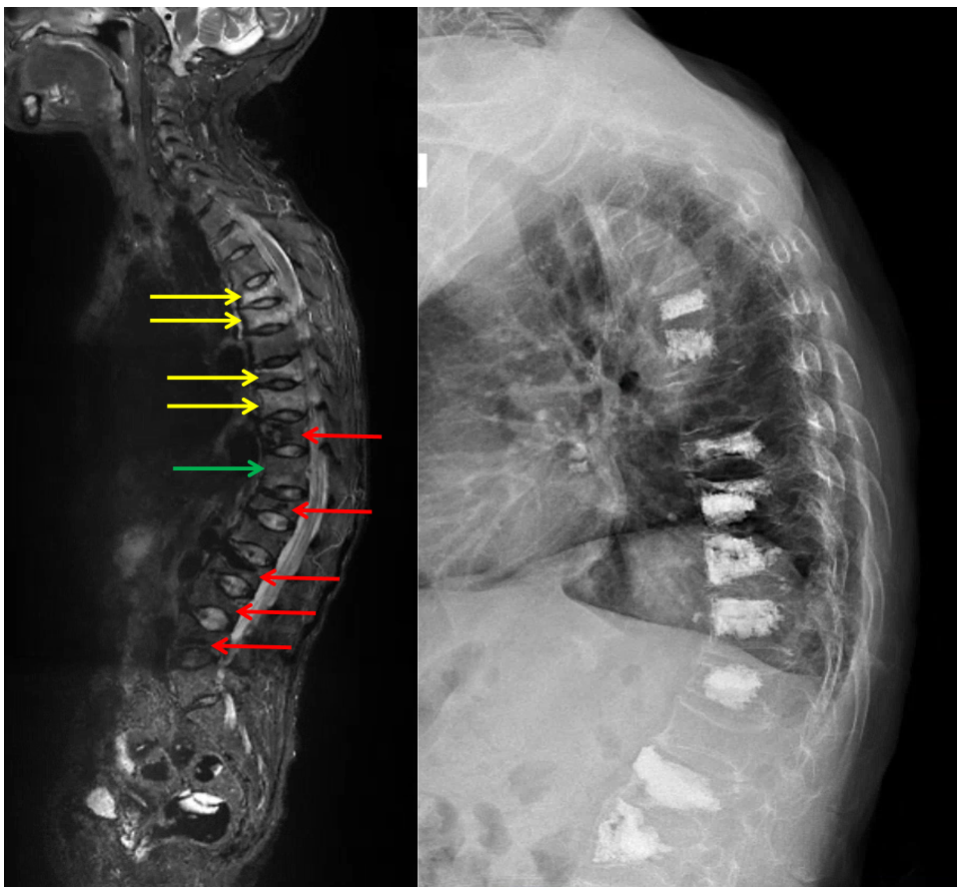

宁海的郑阿姨情况非常典型。年仅58岁的她,压缩性骨折比很多七八十岁的患者还严重,短短两年间,已有5个椎体做过“骨水泥”手术。此次腰酸背痛忍了一个月后,她竟又被查出4个新发骨折,还有1节椎体也已经出现骨水肿,如不进行干预,骨折的结局也在所难免。

经过“骨水泥”手术后,郑阿姨的脊柱遍布“骨水泥”痕迹,虽暂时缓解了疼痛,但身高缩了近10厘米,驼背畸形也已无法纠正

图片左图红色箭头是郑阿姨已做过“骨水泥”手术的5个椎体,黄色箭头是4个新发骨折,绿色箭头是出现骨水肿的T11椎体。右图可见,郑阿姨的脊柱已遍布“骨水泥”。